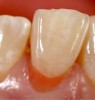

Fig 12. The layer of gingival-colored composite was placed at the base of the restoration to counteract the modulus of elasticity and establish the pink shade. It was sculpted to the margins and light-cured.

Figure 12

Fig 13. To create the sulcus and microtexture, a second layer of composite was placed using a microplacement instrument, working around the margins cervically, and then cured.

Figure 13